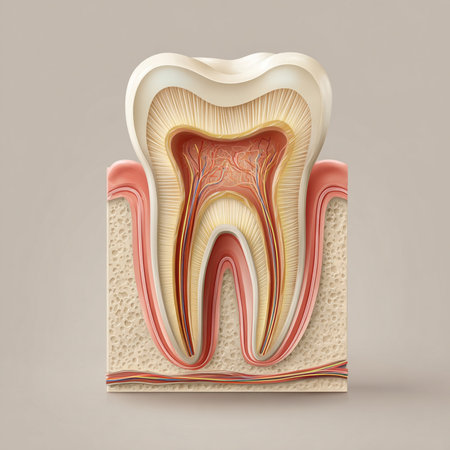

Detailed anatomical model showing human tooth structure, emphasizing root canal system. Ideal for educational purposes in dental hygiene and anatomy studies.

A close-up view of an anatomical model of a human molar tooth's cross-section. The white enamel cap transitions to yellow dentin, revealing the red pulp chamber and root canals within. The surrounding bone structure is depicted with porous texture in beige and red hues. The background is a solid, deep blue.

Detailed depiction of a tooths anatomy highlighting its internal structure and layers.

This image presents a detailed anatomical model of a human tooth, highlighting its layers in a contemporary dental environment for educational purposes.

Dental tooth cross section model showing enamel, dentin, pulp, gum and root structures against a soft colorful bokeh background for oral health education and dentistry study

A detailed dental model illustrates the anatomy of a human tooth highlighting its inner structure including roots and nerves. This model is used for educational purposes in a dental clinic.

This image depicts a detailed anatomical model of a human tooth, showcasing the intricate internal structures, including nerves and blood vessels, essential for educational and healthcare purposes.

This artwork intricately depicts the anatomy of a tooth along with its supporting tissues.

Human tooth anatomy model in dental laboratory. 3d render illustration.

Human tooth cross section. 3d illustration

This image provides a detailed cross-section view of a human tooth, revealing the inner anatomy including the root pulp and surrounding bone structures. It is an educational and informative visual aid

Detailed cross-section of a human tooth displaying enamel, dentin, pulp, and root anatomy. Educational medical illustration on a gradient blue background.